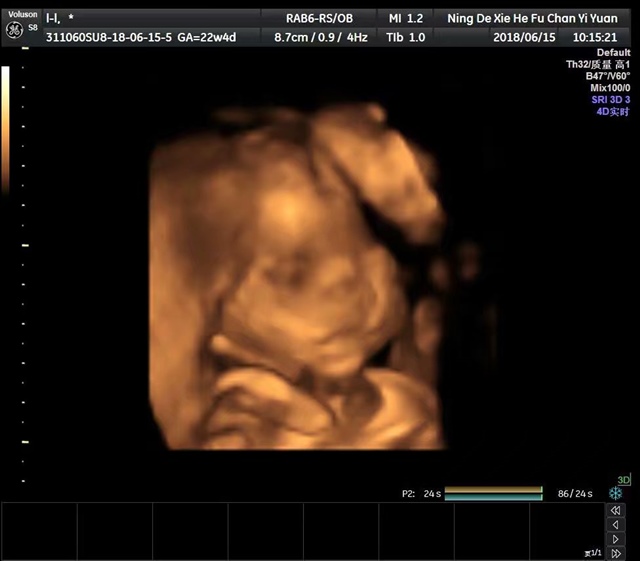

孕22周+3天

女宝么